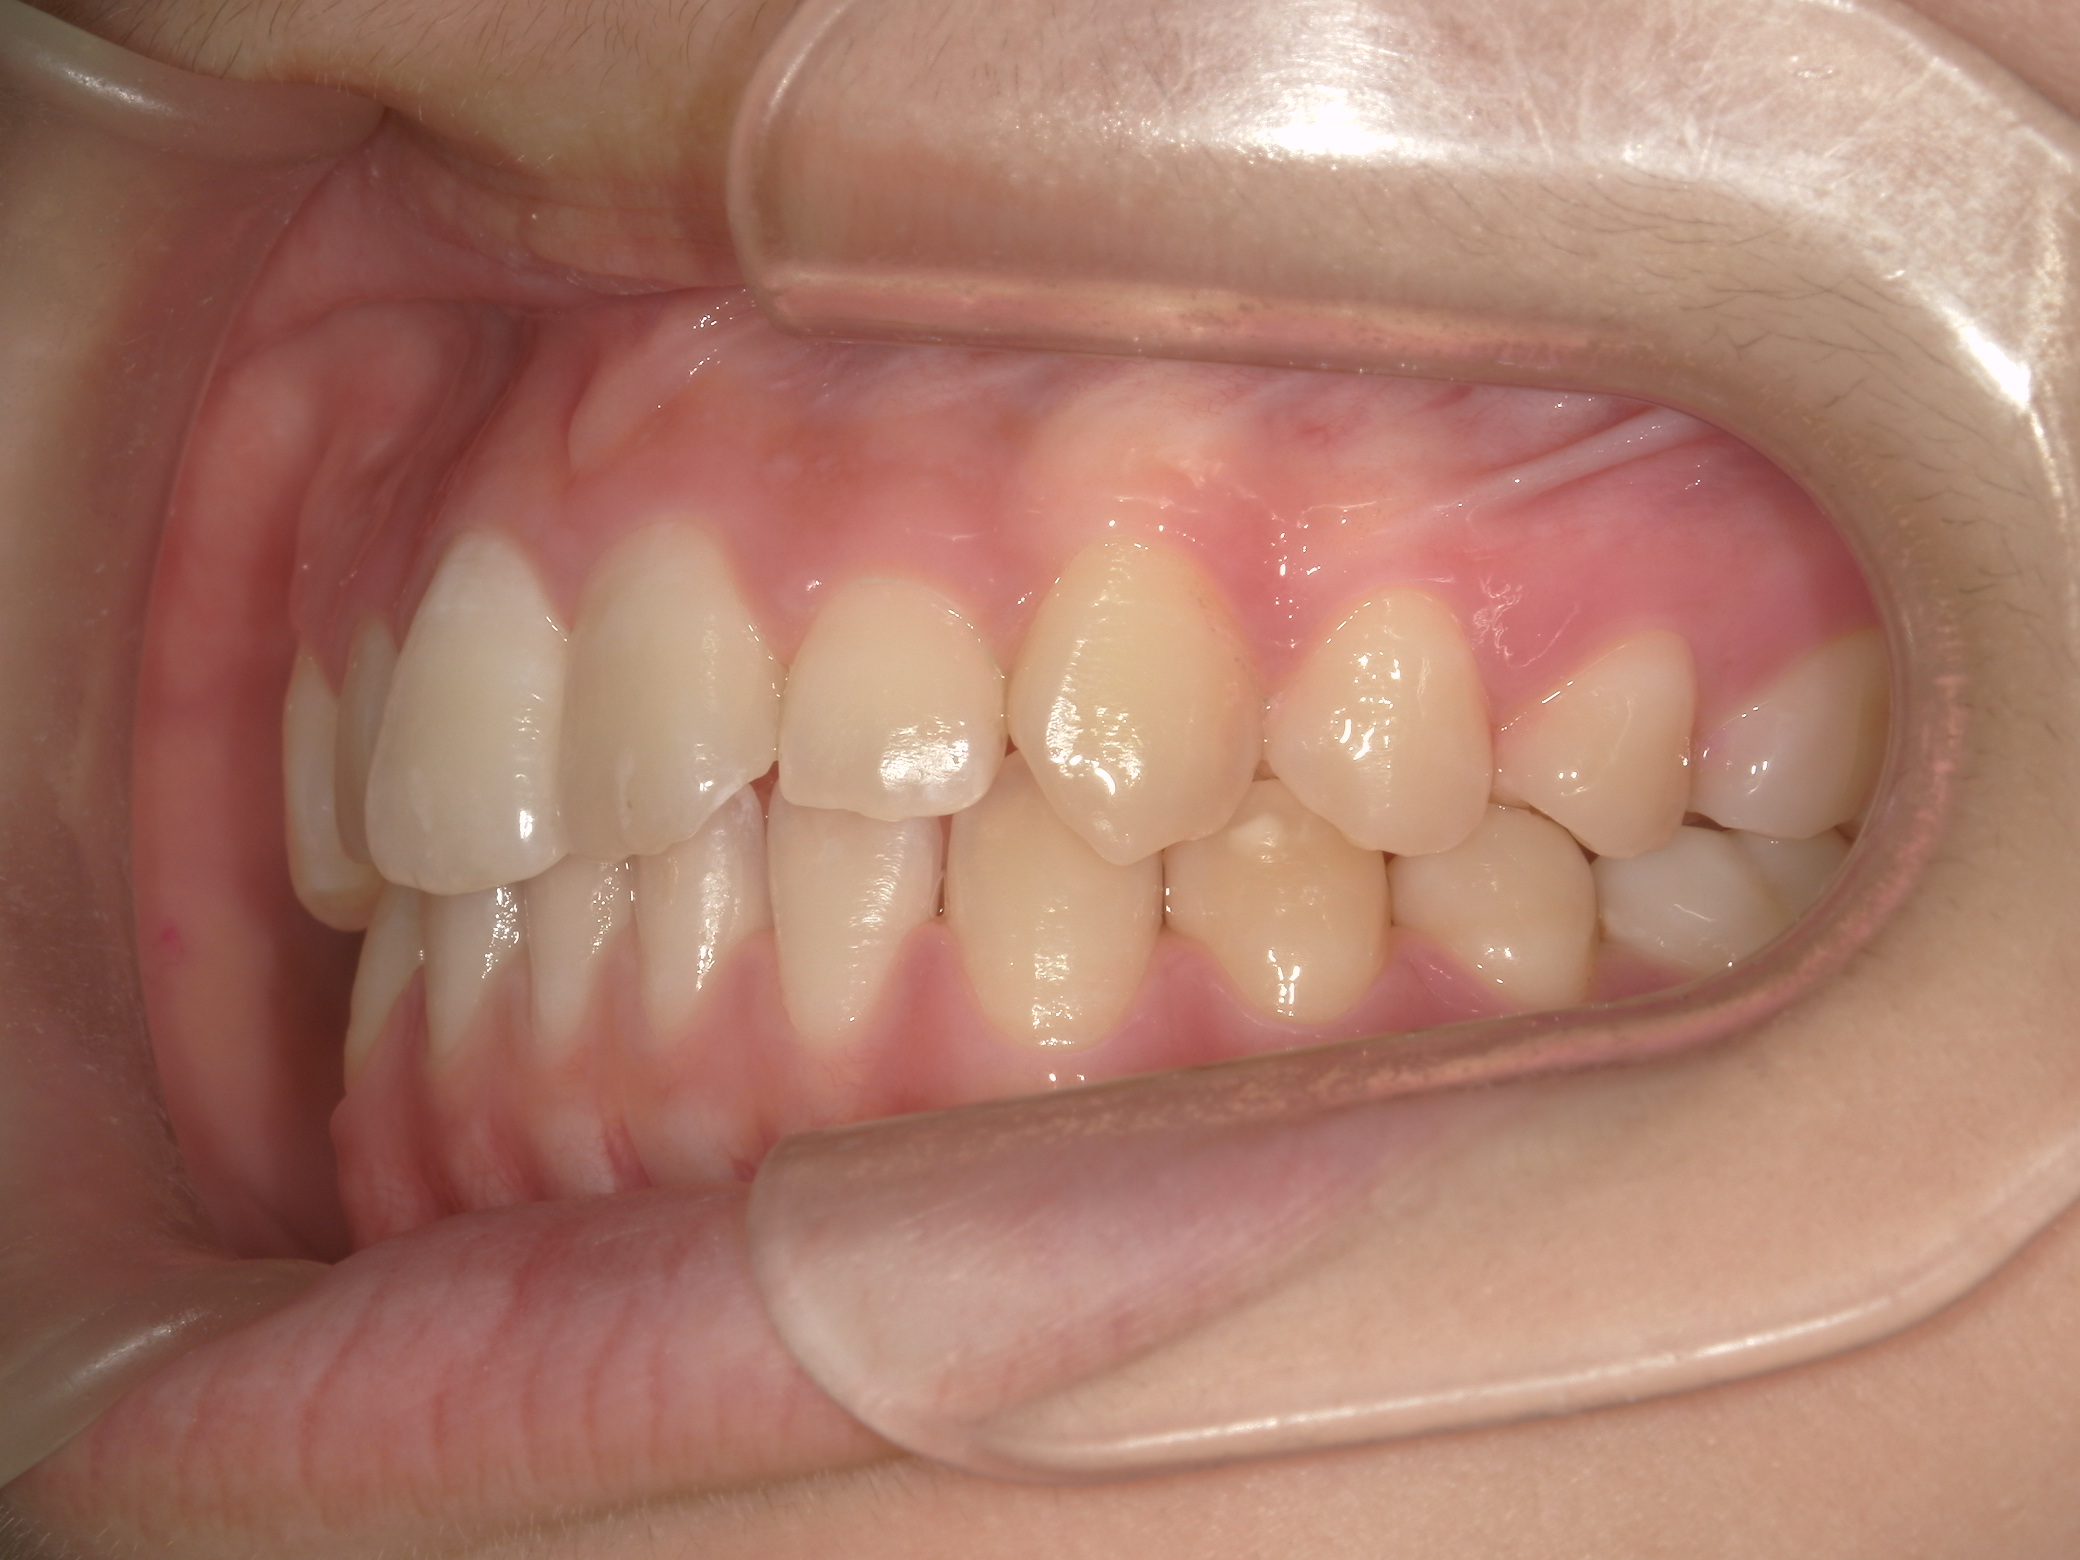

【小学生】マイオブレース矯正 受け口を改善 ①

小学生で開始

マイオブレース

受け口

1期治療のみで改善

Before

After

治療期間

1年11カ月年

治療開始

10歳

種類

マイオブレース矯正

使用装置

機能矯正装置

コメント

毎日装置の装着と MFT 口腔筋機能療法 に取り組んでくれたためスムーズに終わりました。

上顎前歯の並びをもう少し別の装置で改善することも提案しましたが、本人、保護者の方ともに

今の歯並びで満足しているということだったのでこれで終了しています。

MFTを頑張ってくれたため、お口の筋肉バランスもよく、後戻りもしていません。